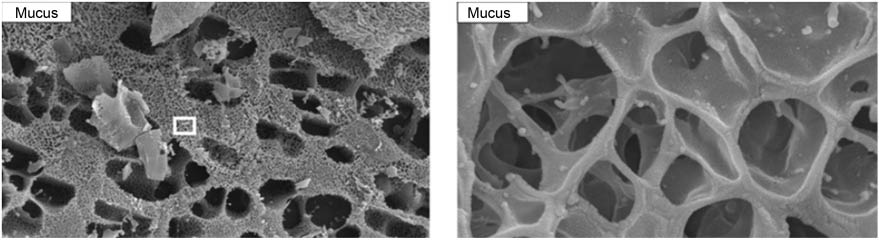

The mucus gel pore size (size filtering), on the one hand, and polyvalent particle-mucus interactions (electrostatic and hydrophobic filtering) on the other, represent the governing mechanisms that enable exogenous particulate material to be trapped and immobilized in the viscous mucus layer (81). With regard to the pore size of pulmonary mucus the average mesh spacing remains a point of discussion, in part because the sample preparation protocols for the imaging techniques used to estimate the pore size (e.g., scanning electron microscopy, SEM) alter the native structure of the gel layer during the dehydration and fixation processes (72). Mucus mesh pore sizes for cervicovaginal mucus has been suggested to be around 350 nm, whereas human CF mucus and rhinosinusitis mucus have been estimated to form a mesh with an average spacing of approximately 150 nm (44). Recent data from Kirch et al. using cryogenic SEM (cryo-SEM), which allows for unbiased determination of the native mucus structure, has revealed a highly heterogeneous pore size for respiratory mucus ranging from pores of approximately 100 nm to voids of several micrometers in diameter (Figure 4). In this study, the authors highlighted the significant thickness and rigidity of the polymer scaffold that resulted in the entrapment of all types of studied nanoparticles (size range 170–500 nm) (80).

Figure 4 Representative cryo-SEM images of pulmonary mucus.The cryo-SEM images of mucus show the strongly heterogeneous nature of mucus polymer mesh (left image). Large as well as very small pores can be observed (left image). Furthermore, the enlarged view of the mucus (right image, representing the area on the left image indicated by a square) shows a thick wall of the polymer scaffold (Scale bar: left 10 μm; right 500 nm.). From reference (79), reprinted with permission from PNAS.

Representative cryo-SEM images of pulmonary mucus.

The cryo-SEM images of mucus show the strongly heterogeneous nature of mucus polymer mesh (left image). Large as well as very small pores can be observed (left image). Furthermore, the enlarged view of the mucus (right image, representing the area on the left image indicated by a square) shows a thick wall of the polymer scaffold (Scale bar: left 10 μm; right 500 nm.). From reference (79), reprinted with permission from PNAS.